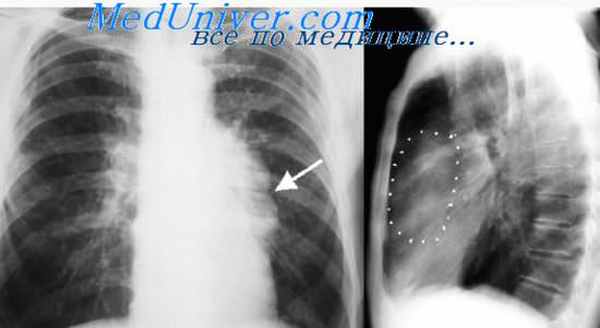

признаки сдавления возвратного гортанного нерва и др. Рентгенологически неврогенные

опухоли характеризуются гомогенной интенсивной овальной или округлой тенью, тесно

примыкающей к позвоночнику.

Для диагностики опухолей средостения (рис. 4.16) применяют многопроекционное рентгенологическое обследование, КТ. Решающую роль в диагностике играют КТ и УЗИ. Для морфологической

Рентгенограмма опухоли средостения. Наибольший диаметр тени опухоли совпадает с тенью средостения, края тени образуют со средостением тупые углы (рентгенологический симптом Ленка)